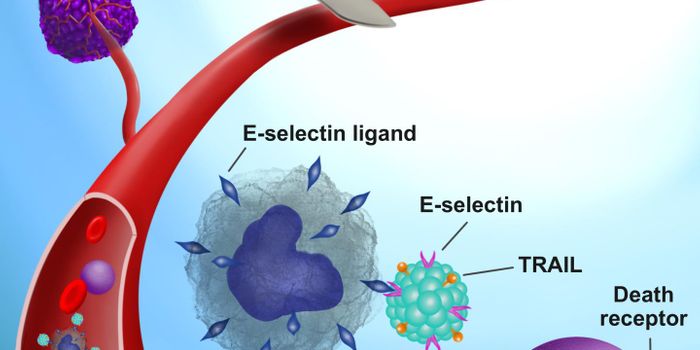

AUG 11, 2019Cell & Molecular BiologyCancer is most deadly when it metastasizes, which can happen after tumor-removal surgery. It's a serious challenge for m ...